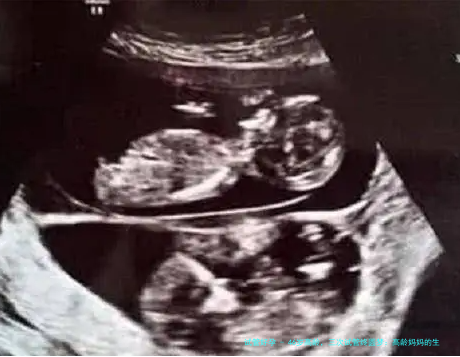

先说说李女士的例子吧。她今年46岁,是一家公司的高管,年轻时忙于打拼,等到想当妈妈时,才发现年龄成了大问题。她告诉我:『第一次做试管时,我满怀希望,结果却失败了,那种失落感真的难以形容。』第二次尝试时,她调整了心态,加强了身体调理,但还是没成功。第三次,她吸取了前两次的教训,配合医生建议,最终在去年底成功怀孕。李女士的经历让我感慨万千:高龄生育不只是医学问题,更是一场心理战。她笑着说:『现在回想起来,那些失败都是宝贵的经验,让我更珍惜现在的幸福。』这种坚持,不正是许多高龄妈妈的缩影吗?